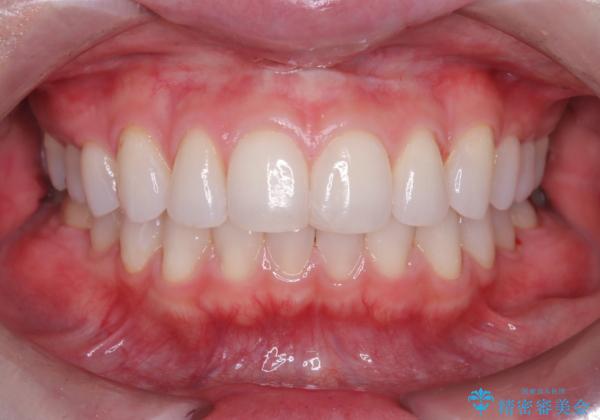

エアフローを行い、着色やバイオフィルム・歯垢(プラーク)が除去され歯の表面に艶が出ました。

エアフローは、着色やバイオフィルム(微生物の集まり)や・歯垢を除去するので歯本来の色に近づけるだけでなく、むし歯予防にもなります。

患者様にも、お口の中がスッキリして気持ちよかったと好評でした。